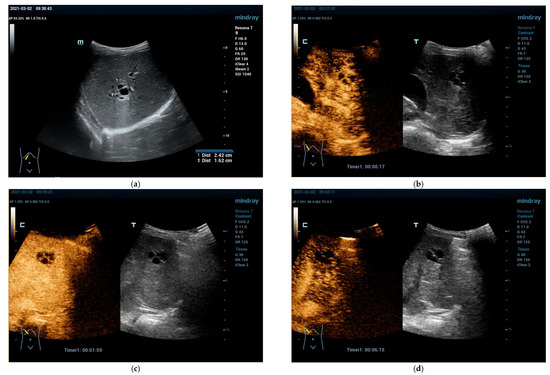

4.3.1. Hepatic Hemangioma

4.3.2. Congenital Hepatic Hemangioma

4.3.3. Infantile Hepatic Hemangioma

4.4. Vascular Malformations Other than Hemangioma